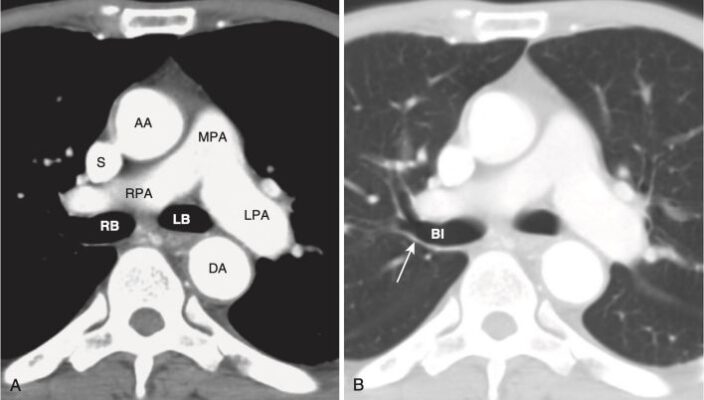

Mức tim cao (Hình 9)

- Ở mức này, có thể xác định được nhĩ trái, nhĩ phải, gốc động mạch chủ và đường ra của thất phải (right ventricular outflow tract, RVOT).

- Tâm nhĩ trái chiếm phần sau và trung tâm của tim. Có thể thấy một hoặc nhiều tĩnh mạch phổi đổ vào nhĩ trái.

- Tâm nhĩ phải tạo thành bờ phải tim và nằm ngay bên phải của nhĩ trái.

- Đường ra của tâm thất phải nằm trước, bên và trên so với gốc của động mạch chủ. Van động mạch phổi nằm trước, bên và trên van động mạch chủ .